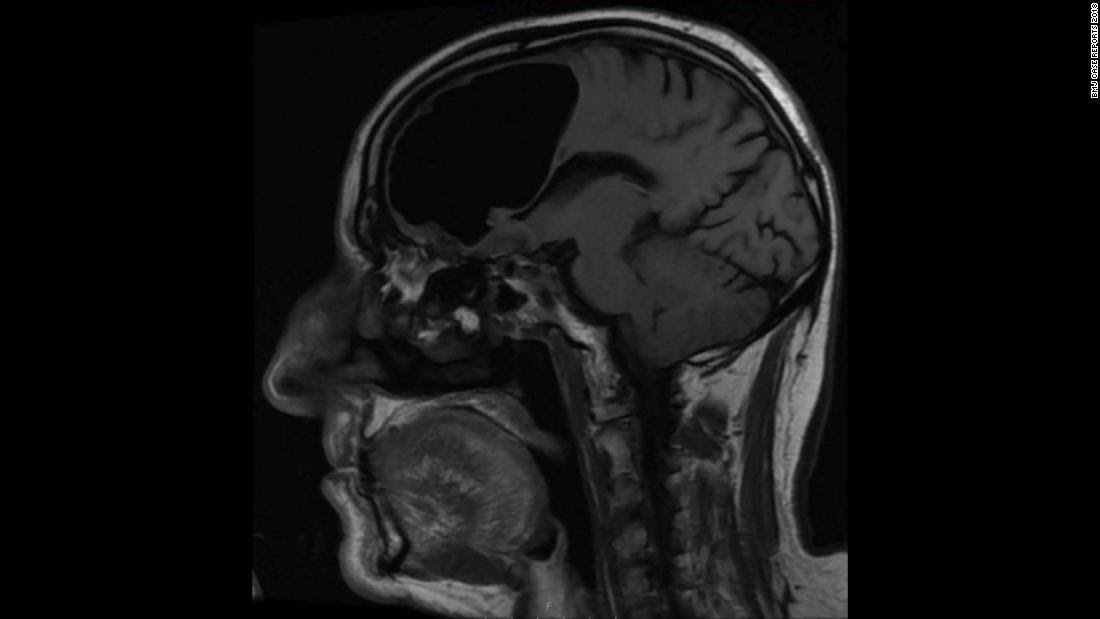

أظهر التصوير المقطعي المحوسب لدماغ المريض وجود جيب كبير من الهواء - يسمى أيضًا القيلة الهوائية - في الفص الأمامي الأيمن للمريض يبلغ طوله حوالي 3 بوصات ونصف.

كان الجيب الهوائي خلف الجيب الجبهي مباشرة وفوق الصفيحة المصفوية، التي تفصل تجويف الأنف عن تجويف الجمجمة.

وأظهر التصوير بالرنين المغناطيسي لدماغ الرجل أيضًا ورمًا عظميًا صغيرًا حميدًا، أو ورمًا عظميًا، تشكل في الجيوب الأنفية للرجل وكان يتآكل عبر قاعدة الجمجمة، مما تسبب في تسرب الهواء إلى تجويف الجمجمة، وفقًا للتقرير.